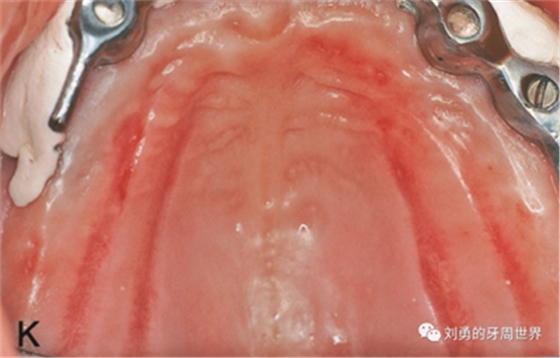

6、剪刀去除殘留的條狀牙槽粘膜(I),骨膜床預(yù)備結(jié)束(J)

7、剪刀去除骨膜上剩余的肌肉組織纖維(K),可以將翻開的半厚瓣剪掉或根向縫合在前庭溝的骨膜上。